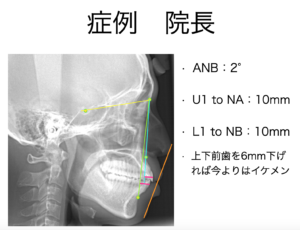

とりあえず、叢生を治そうと思って軽い気持ちでインビザラインを始めようと思ったのですが、セファロ分析という横顔のレントゲン写真を用いた分析を行ったところ、理想値を達成するためには、6mmも上下の前歯を後ろに引く必要があるという結果がでしました。6mmも後ろに引けば、口元が下がり、現状よりはイケメンになれます。

しかし、上下左右4本の歯の抜歯が必須でした。歯を抜かなければ6mmも後ろに下げられません。

軽い叢生を除去するだけなら10ヶ月、歯を抜いた場合は3年・・・。

もともと、そこまで治すつもりもありませんでしたので、私はイケメンになることを諦めて、叢生だけを治してインビザライン治療を終えました。